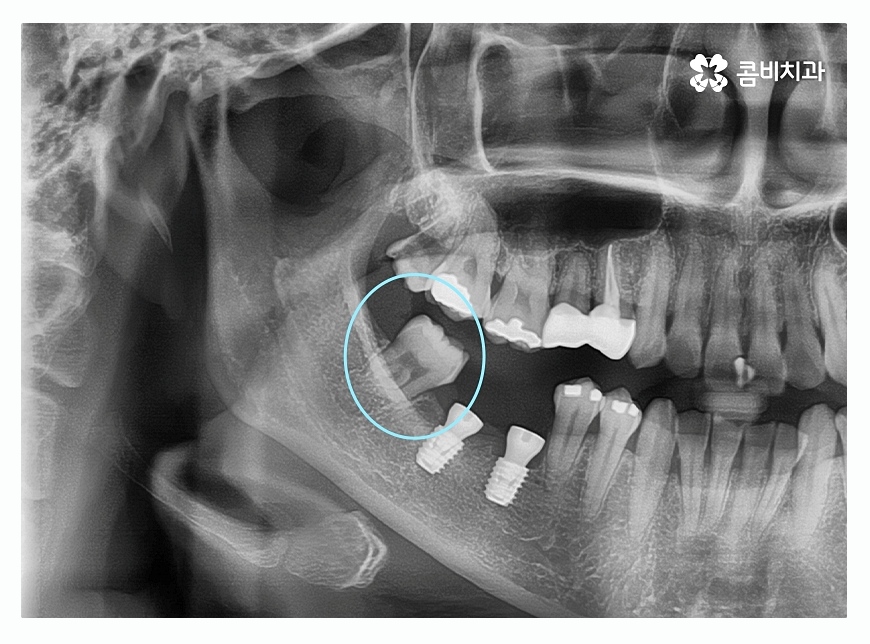

위 이미지에서 보시는 것처럼 치주염으로 인하여

잇몸뼈가 많이 내려간 경우 음식물이 잘 끼고 관리가 잘 안되면서

치아가 깊게 뿌리내리지 못해 흔들리게 되고

치아가 제대로 된 기능을 하지 못하여 발치까지 진행되는 경우가 있는데

위 환자분도 사랑니가 이런 경우에 해당되어 발치를 진행한 사례라고 할 수 있어요.

임플란트종류에 있어서 잇몸뼈의 상태가 관건이라고 할 정도로

큰 부분을 차지하게 되는데 젊은 분들의 경우

충치나 외상으로 인해 치아를 잃게 되는 경우가 많기 때문에

임플란트종류 중에서 원데이임플란트라고 불리는 발치 후 즉시 식립을

하는 경우도 있지만 치주염으로 인해 치아를 잃게 된 경우에는

즉시 식립이 어렵거나 뼈이식을 해야 할 수 있어요.